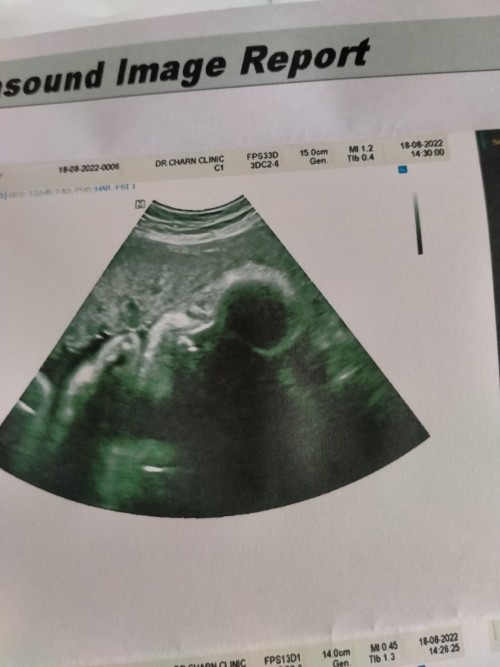

นี้33กว่าแล้วยังไม่รุ้เพศ100%เลยจร้าน้องนอนคว่ำจะซาวให้อีกทีตอน9เดือนนู้นเลยรอวันที่9กันยาน่าจะซาวให้แล้ว

30W1วัน คะ ไปซาวมาวันนี้ น้องเอามือบังหน้าไว้ไม่มีรุปมาอวดเลย